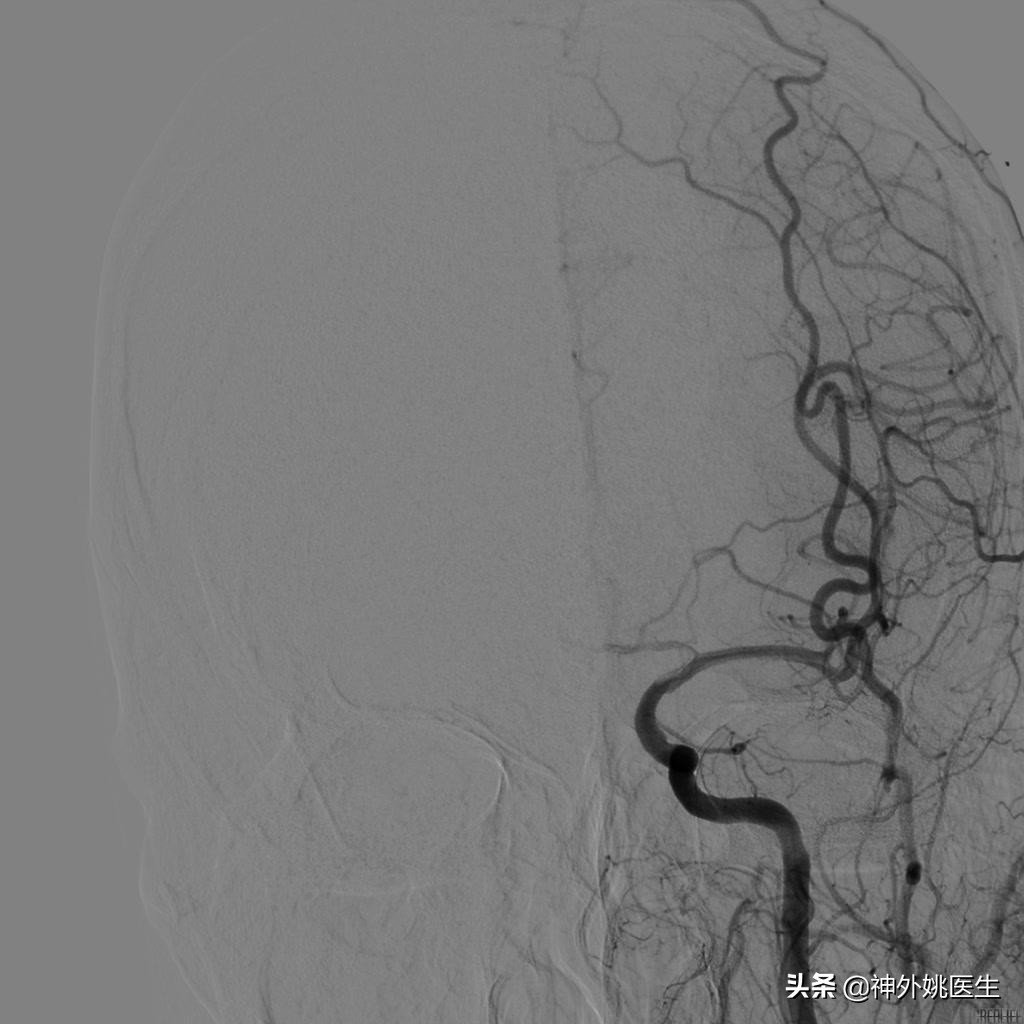

术前DSA检查:(图3-6)

图3 左颈内动脉起始段重度狭窄。

图4 右颈动脉造影示前交通动脉开放,左侧A2以远显影,通过左侧A1至M1以远亦显影。